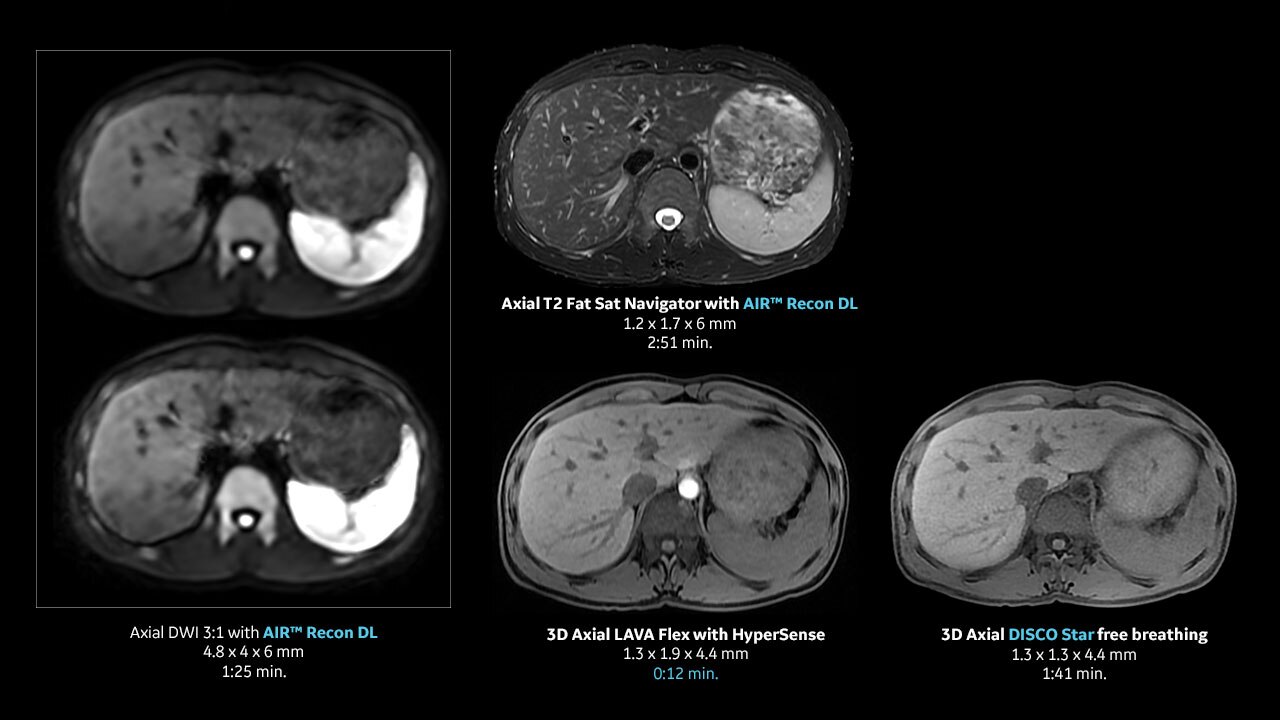

With access to the latest advanced AI technology, you can scan all anatomies and achieve pin-sharp images. Our pioneering Deep Learning-based reconstruction algorithm AIR™ Recon DL accelerates scan time and puts patients at ease.